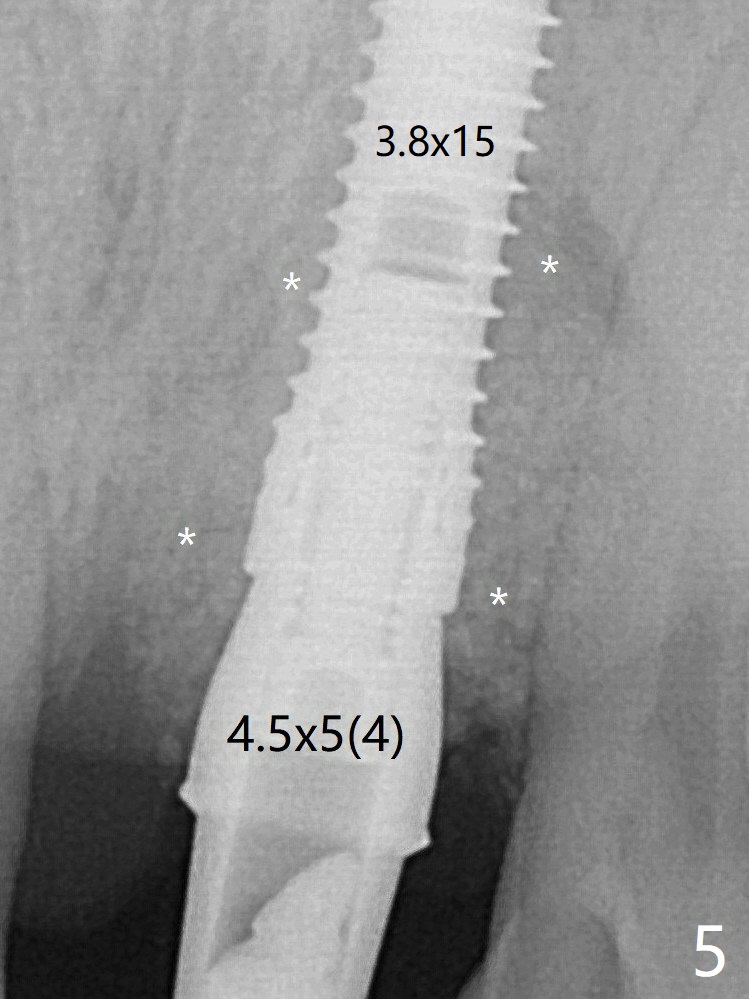

After placement of a 3.8x15 mm implant, PRF is laid against the inner surface of the buccal defect and allograft (Fig.5 *) is packed mainly in the buccal gap before and after insertion of a 4.5x5(4) mm abutment. The bone graft remains in place 3.5 and 4.5 months postop (Fig.11,12 *). Between 3 and 4 months postop, the mesial surface of the abutment has been trimmed (Fig.12 >). Since the mesial surface of the tooth #10 will be reduced (white curved line) to correct the upper dental midline, an angled abutment (red line) seems to be necessary to shift the provisional distal. The socket at UL1 seems to have healed except the most coronal 1 year 3 months postop (Fig.14 *).